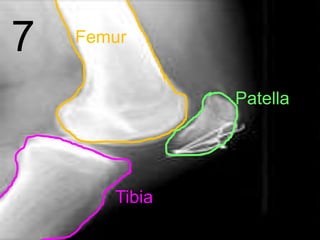

7 Femur

Patella

Tibia